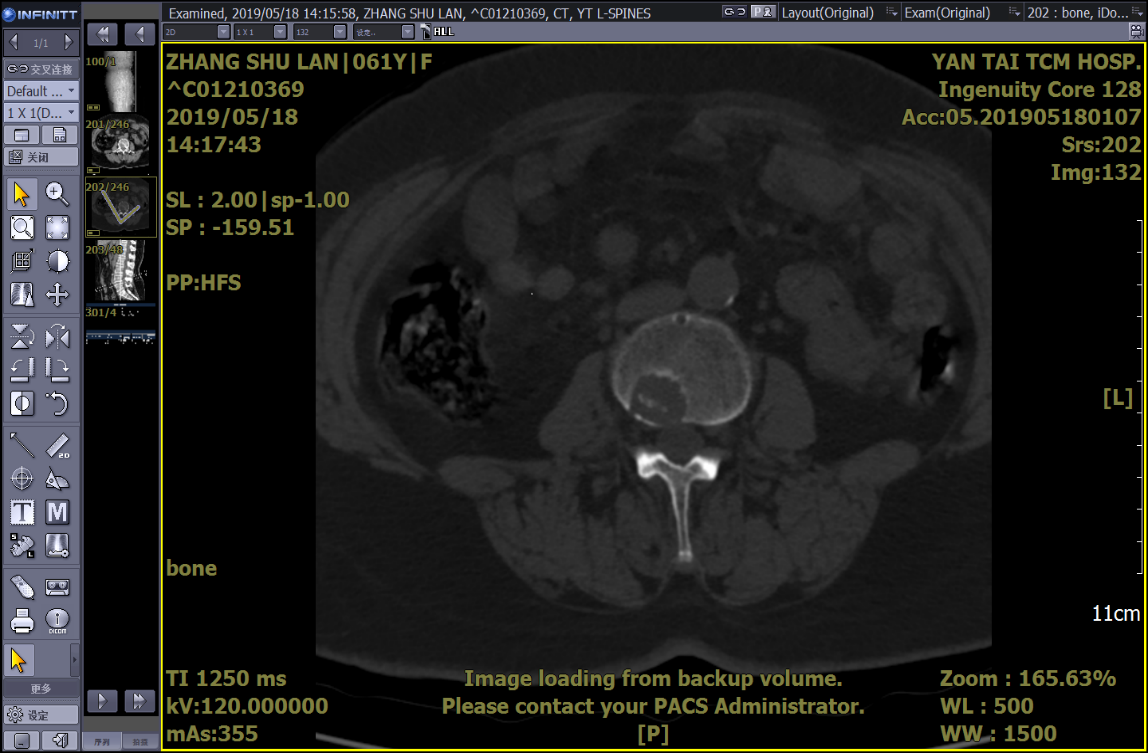

PET-CT示:1.腰3椎體(tǐ)局限性骨質破壞,FDG代謝輕度增高;股骨頸局限性骨質破壞,周圍軟組織受侵、腫脹,局部條狀骨骼密度影(yǐng),FDG代謝增高。右側顱骨及腰椎多個椎體(tǐ)骨質破壞、胸椎多個椎體(tǐ)低密度影(yǐng),FDG代謝不高。考慮骨髓瘤?

床頭攝片:右股骨小轉子遊離(lí),請(qǐng)結合臨床。

因患者存在椎體(tǐ)及股骨頸骨損,患者目前隻能扶杖行走,爲了能夠更好地改善患者生(shēng)活質量,預防病理性骨折發生(shēng),需要對如(rú)下骨損進行外科幹預治療。

針對多發性骨髓瘤患者的椎體(tǐ)及髋關節骨質破壞情況,各科室主任、骨幹紛紛提出積極下一步治療手段,最後經過多學科討(tǎo)論,主要可(kě)選擇的治療手段有:行髓内釘固定、骨水泥固定、腫瘤侵蝕區域的放(fàng)射性粒子植入治療、換髋關節等方法。具體(tǐ)選項要根據患者的實際情況及經濟狀況和家屬商量決定。